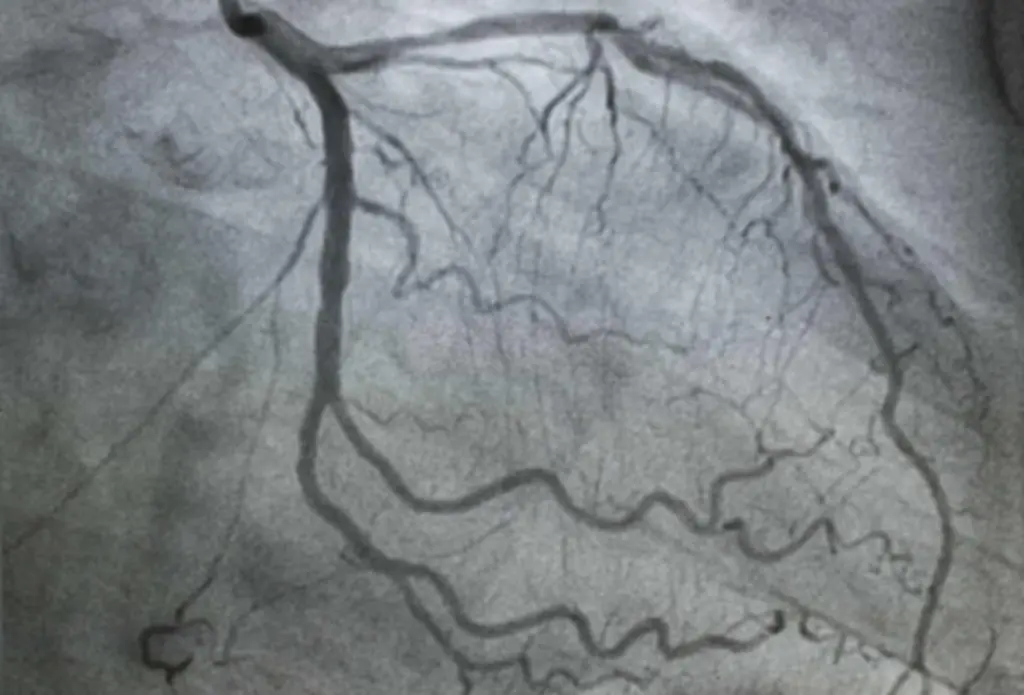

- تمكن من تصوير الأوعية التاجية لفحص القلب أو الأوعية الدموية عن طريق حقن صبغة من خلال القسطرة.

- بمجرد وضع القسطرة في مكانها ، يمكن للطبيب استخدامها لإجراء الاختبارات التشخيصية مثل تصوير الأوعية وصمامات القلب وغرف القلب باستخدام جهاز أشعة سينية خاص.